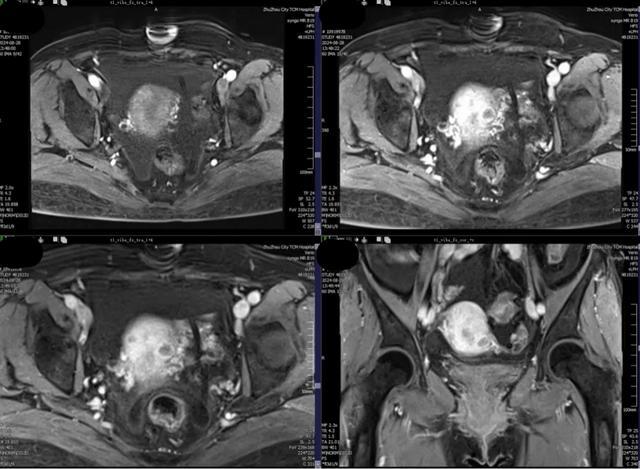

磁共振检查获取的是整个盆腔的数字信息,可以多方位、多参数的了解子宫及子宫肌瘤的情况,对于子宫肌瘤的生长发育情况以及是否影响后续生育更是有独到的见解,对于年轻的患者来说更是不可或缺的。

磁共振检查具有超高软组织分辨率,更是能够进行多方位、多参数的检查来评估病灶,给出更加精准的诊断意见,有利于盆腔肿块的发现、病变定性和肿瘤分期。

常规超声检查报告仅由检查描述、报告配图、结论构成,但是超声检查是一个动态获取过程,单靠文字以及配图无法完整复现检查中获取的信息量。与常规超声检查相比,磁共振检查一次检查能够获得整个盆腔的数字资料,更加客观准确的判断子宫肌瘤大小数目以及位置形态。

磁共振检查能够辅助判断一个病灶是良性还是恶性子宫肌瘤,通过磁共振增强检查可以使有血供的部位增强显影,一方面鉴别了肌瘤和肉瘤,一方面也能给临床医生更好的术前评估设计子宫切口,以合适的切口进行子宫肌瘤的剔除。